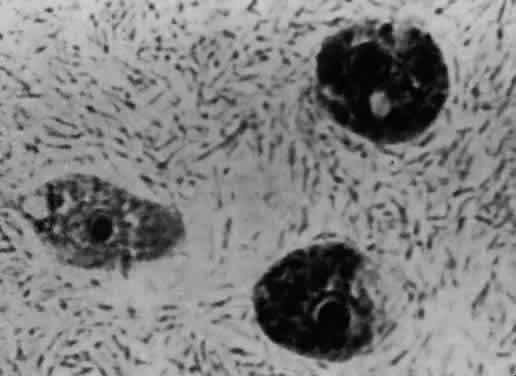

Acanthamoeba organisms are small and resilient, with a wide distribution in the environment.1,2 The protozoan's life cycle is characterized by a transformation from active trophozoite to dormant cyst. The irregularly shaped trophozoite, which is 15 to 45 μm in diameter, is slowly motile (Fig. 1). The cyst is 10 to 25 μm long and has a thick double-walled external structure consisting of an outer wrinkled ectocyst and inner polygonal endocyst (Fig. 2).3,4 Transformation from the trophozoite to the cyst stage enhances survival in unfavorable circumstances, which include wide temperature ranges, desiccation, food depletion, pH changes, low oxygen concentration, and cell crowding.5

Fig. 1. Acanthamoeba trophozoite.